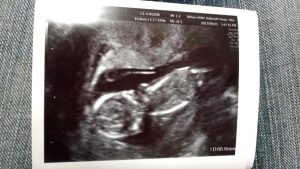

9/25(月)付けで12週6日目。

はじめてエコー画像で動いている胎児を見ましたが、めちゃくちゃピョンピョンと元気よくジャンプしていました。

胎児の大きさは6cm~7cm位で順調に成長しています。